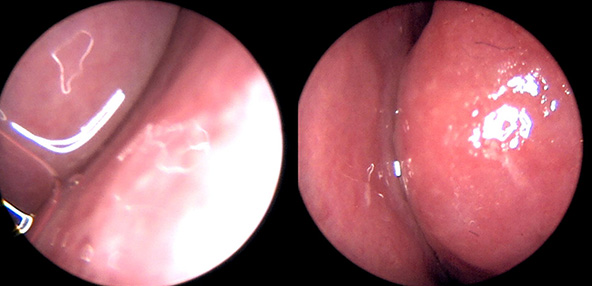

※ 비중격 비염 수술 후 생길 수 있는 부작용으로는 출혈, 감염, 염증이 있을 수 있습니다.

본 사진은 의료기관에서 진료를 본 환자이고, 전후 사진 인물이 동일인이며,동일조건에서 촬영이 되었습니다.